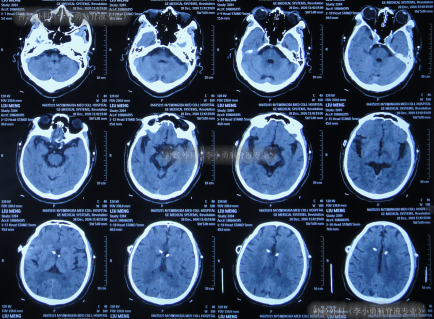

术后次日查头颅CT示脑室有缩小(图-4),意识也有好转。

图-4:2020年12月9日头颅CT